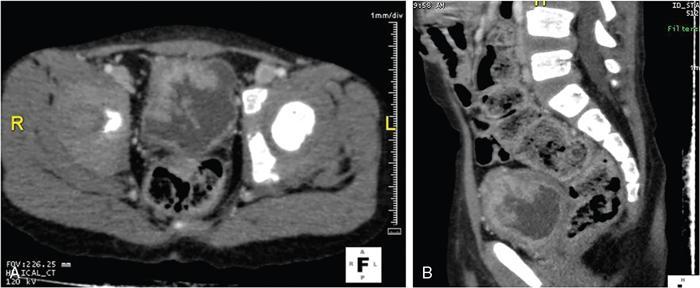

Anmol Bhatia, Kushaljit Singh Sodhi, Akshay Kumar Saxena Congenital as well as acquired anomalies of the bladder and urethra are a significant cause of morbidity in children. Various radiological investigations for imaging bladder and urethra include ultrasonography (US), voiding cystourethrography (VCUG) and intravenous urography (IVU), computed tomography (CT), magnetic resonance imaging (MRI) and contrast-enhanced voiding urosonography. In this chapter, we will discuss and illustrate a wide spectrum of congenital and acquired anomalies of bladder and urethral in children. Foetal allantoic stalk is the connection between the bladder dome and the umbilicus during the embryogenesis. Normally, it gets involuted by the second month of gestation. Depending on the degree of the persistence of this foetal allantoic stalk results in varying types of urachal remnants. The clinical presentation depends on the type of urachal remnant: Fluoroscopy is the best imaging modality for documenting the patency of urachus. However, there may be an underestimation of the exact length of the urachal remnant as inflammation occurring along the tract may block its lumen. CT and MRI are usually not needed for the detection of urachal remnants. However, urachal remnants are usually detected incidentally on CT scan done for other indications. Cystic or solid elongated tubular structure may be seen extending from bladder dome to umbilicus. A focal cystic lesion (Fig. 10.11.3) may be seen in the midline anywhere from bladder dome to umbilicus. In case the urachal remnant present with the symptoms, resection of the entire tract is warranted. Bladder diverticulum are localized outpouching from the bladder wall. They can be single or multiple of varying sizes. A male predominance is seen in comparison to females. It has been traditionally classified into four types: They can be incidentally detected or present with complications including recurrent UTI, urinary retention, incontinence, stone formation, VUR and bladder or ureteric obstruction. Bladder diverticulum should be differentiated from ‘bladder-ears’ in newborn male which is bilateral protrusion of bladder wall into inguinal ring. These are transient and disappear with growth. Appearance of diverticulum depends on cause, location, size and presence of complication features. VCUG under fluoroscopy is most efficient method to demonstrate diverticulum. Fluoroscopic monitoring during all phases including voiding and immediate postvoiding phase is important along with oblique and lateral views. Contained contrast-filled outpouching is seen which may be visible only during voiding phase when urine is forced into diverticulum during bladder contraction. Associated VUR is present in 50% of cases. Round or oval anechoic structure arising in communication with the bladder is seen. Well-defined homogenous structure with fluid attenuation/signal intensity arising from bladder wall (Fig. 10.11.6). Secondary complications like stone formation or rupture can be seen. Surgical removal using intravesical, extravesical or combined approach may be performed along with meticulous repair of bladder wall. Urinary bladder neoplasms are not commonly encountered in children. The majority of bladder neoplasms in children are of mesenchymal origin and overall rhabdomyosarcoma is the most common malignancy (Table 10.11.1). They can be incidentally detected or present with urological symptoms including dysuria, haematuria, incontinence and lower abdominal pain. It can manifest as filling defect in MCU studies done for other indications. Ultrasound is usually the first line investigation with cross-sectional imaging being performed in suspected cases for accurate characterization, localization, disease extent and complication. Histopathological analysis is often needed for final diagnosis. The differential diagnosis of bladder masses includes masses arising from adjacent pelvic structures, variants like ureterocoele or urachal remanent, mass forming cystitis (eosinophilic cystitis, BK virus–associated cystitis), haematoma, calculi or iatrogenic materials (e.g. Deflux used in VUR surgeries). Rhabdomyosarcoma Leiomyoma Neurofibroma IMT Leiomyosarcoma Angiosarcoma Haemangioma Urothelial carcinoma PUNLMP: urothelial papilloma Fibroepithelial polyp Paraganglioma Nephrogenic adenoma PUNLMP, papillary urothelial neoplasm of low malignant potential. Rhabdomyosarcomas are the most common urinary bladder neoplasms in first two decades of life presenting typically at ages 2–6 years and 15–19 years. Syndromic association with Li–Fraumeni cancer syndrome, NF type 1, MEN 2A has been found; however, majority are sporadic in origin. Histological subtypes include embryonal rhabdomyosarcoma (classical, botryoid and spindle cell variant), alveolar and undifferentiated sarcoma types of which embryonal form accounts for 90% of all cases. Locoregional spread to adjacent organs, muscles, regional lymphnodes is seen with distal metastasis to lung, cortical bones and retroperitoneal lymphnodes. Metastasis is found in approximately 10%–20% of patients at time of initial presentation. Overall survival and outcome depend on patient age and histological subtype with patients between 1–9 years of age and embryonal subtype having a better prognosis. Imaging work-up includes CT or MRI pelvis for local disease characterization and extent, CT chest, bone scintigraphy or FDG-PET for metastasis and staging. They commonly arise from bladder trigone and neck area. Ultrasound: They are typically large, intraluminal, multilobulated masses with well-defined margins and homogenous hypoechoic or hyperechoic echotexture. Foci of necrosis or haemorrhage are often seen. Vascularity on colour Doppler is increased. Hydronephrosis and bladder neck obstruction secondary to mass can be found. CT: Bulky heterogenous low attenuation mass that may invade into periurethral or perivesical tissue (Fig. 10.11.7). Calcification is rare.